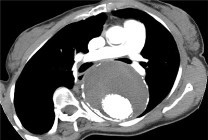

Computed Tomography scans (CT scans), also known as "CAT Scans", are the preferred method of diagnosing an aortic abnormality through imaging.

However, to ensure a better image, a contrast medium (dye) is given intravenously before the image is taken. Therefore, this method may not be used in some patients, such as those with known allergies or kidney problems, for example.

This is now the standard for preparing and planning patients for surgery (both endovascular and open).